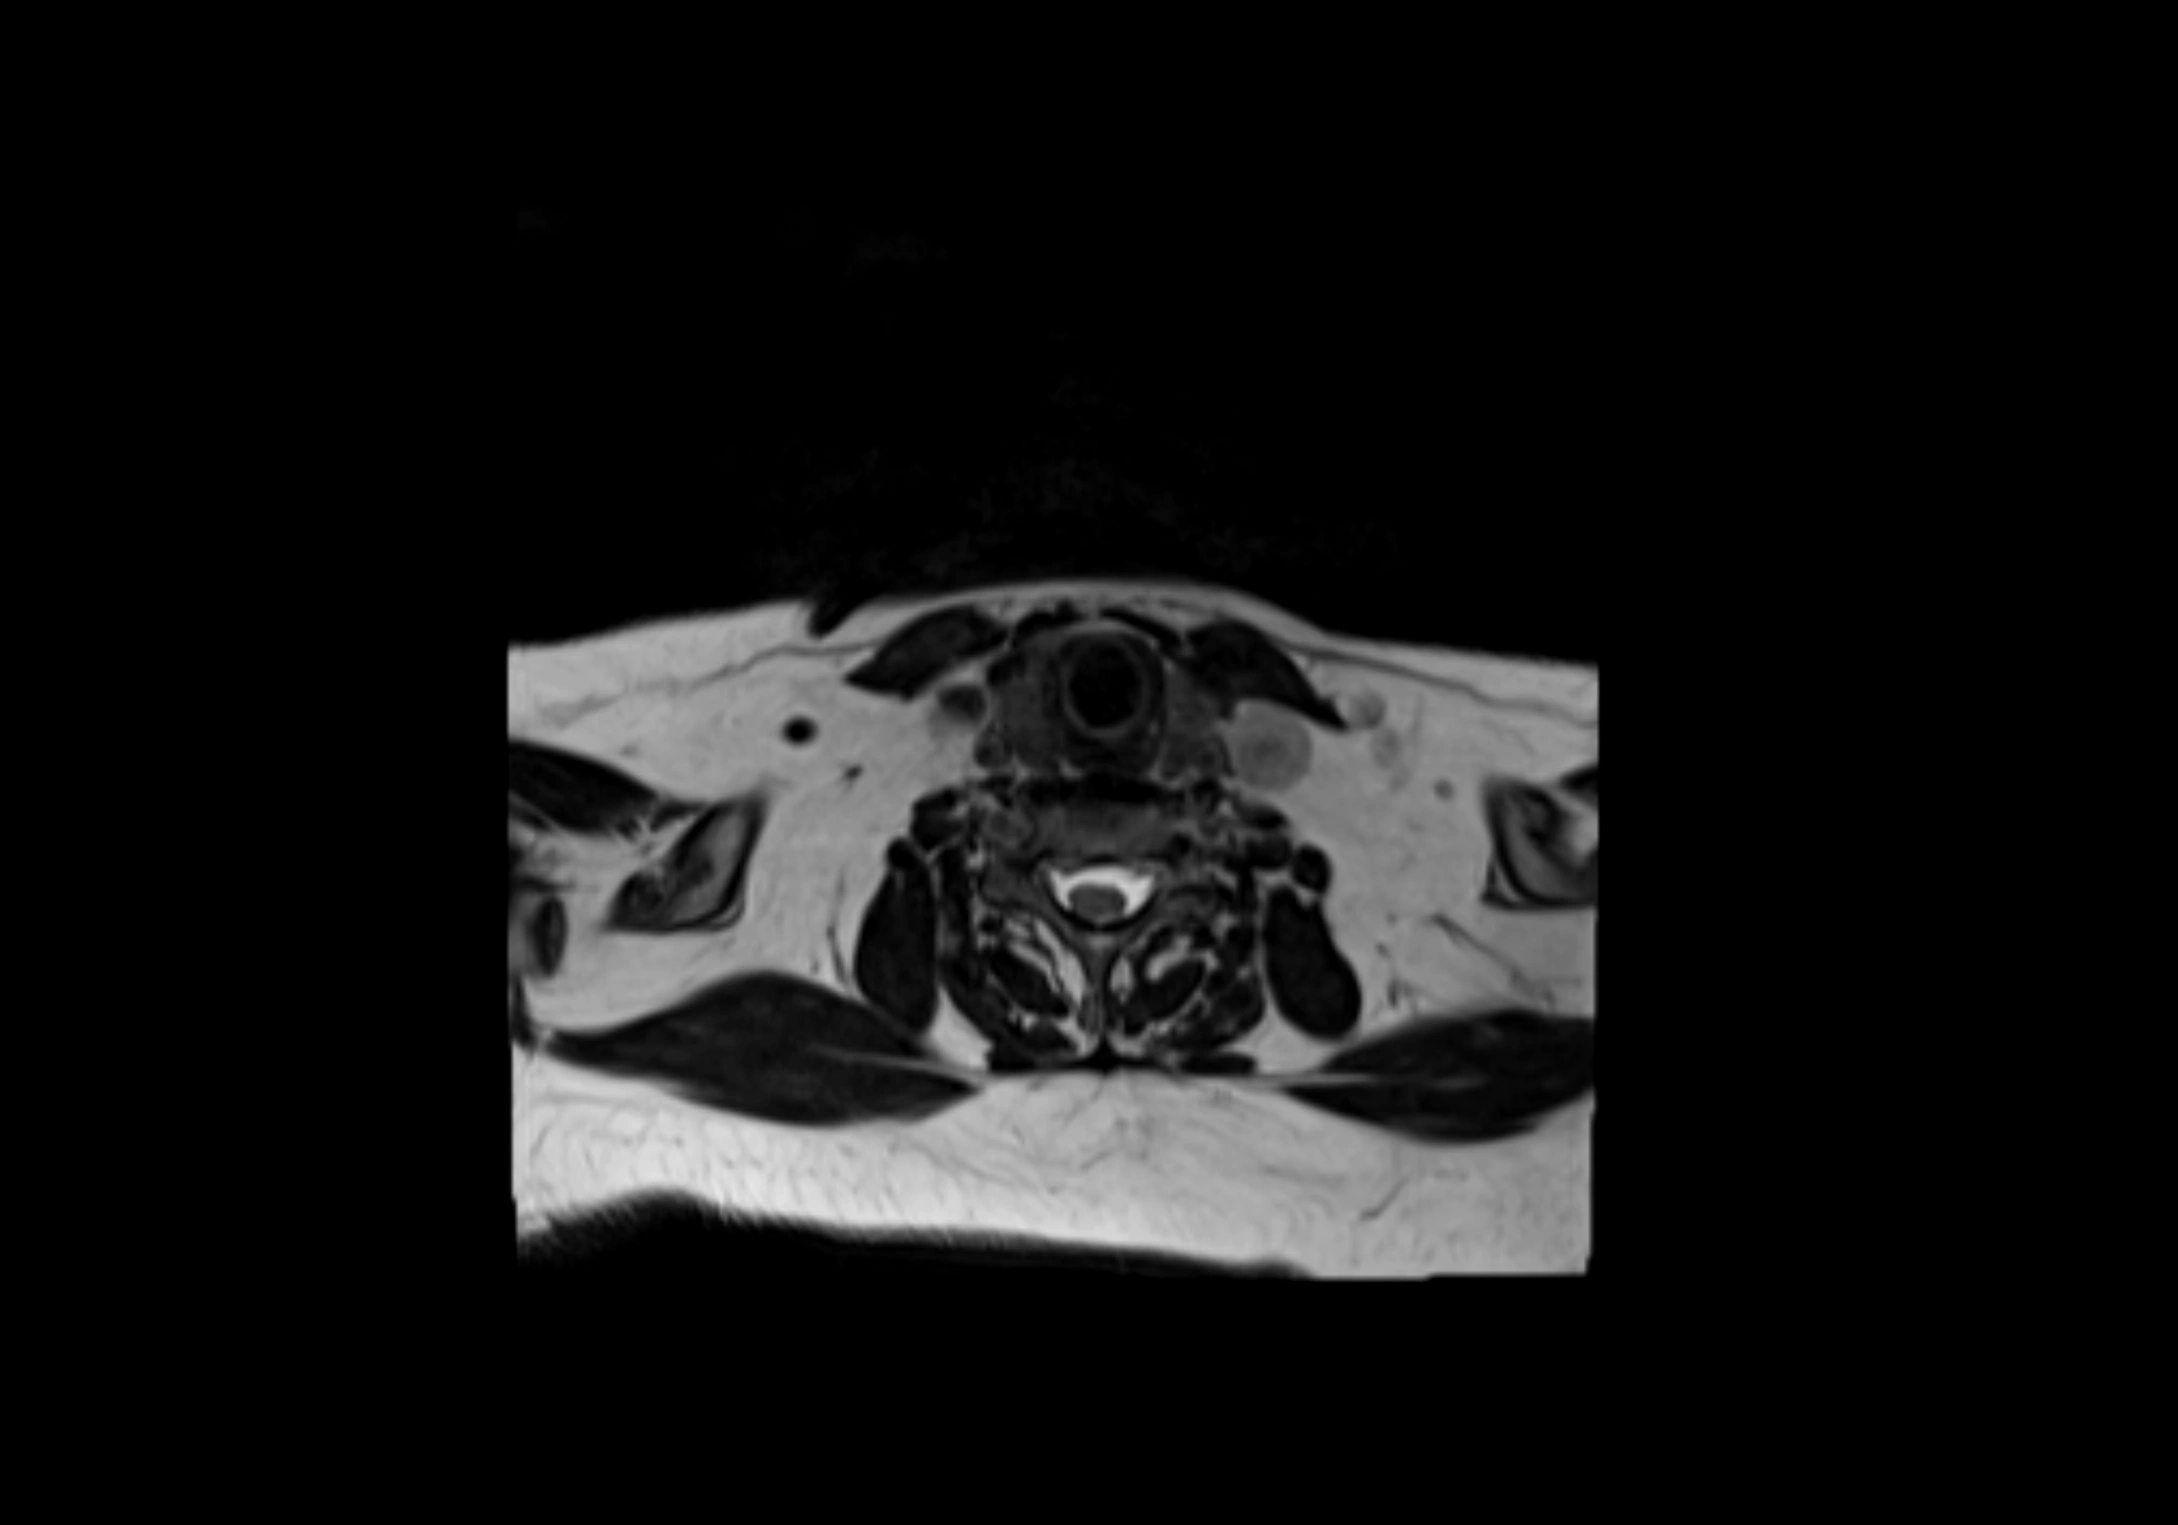

MRI Appearance

T1-weighted images:

• Normal accessory nodes appear as small, oval hypointense to intermediate signal structures within subcutaneous fat

• Surrounded by hyperintense fat, enhancing contrast for visualization

T2-weighted images:

• Nodes show intermediate signal, with surrounding fat bright

• Useful for detecting edema, inflammation, or infiltration

MRI images

image